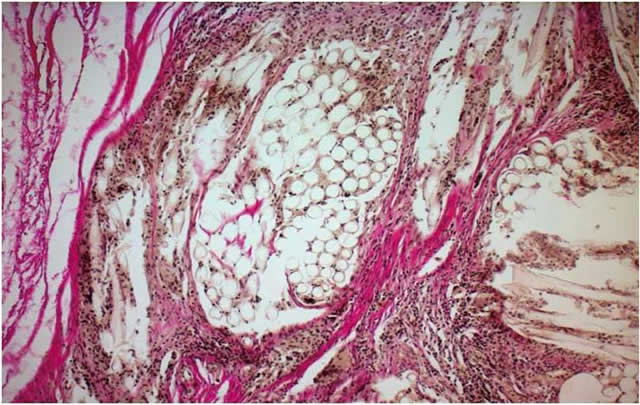

Карнификация Легкого: Микропрепараты и Диагностика

Раздел: Калейдоскоп образов